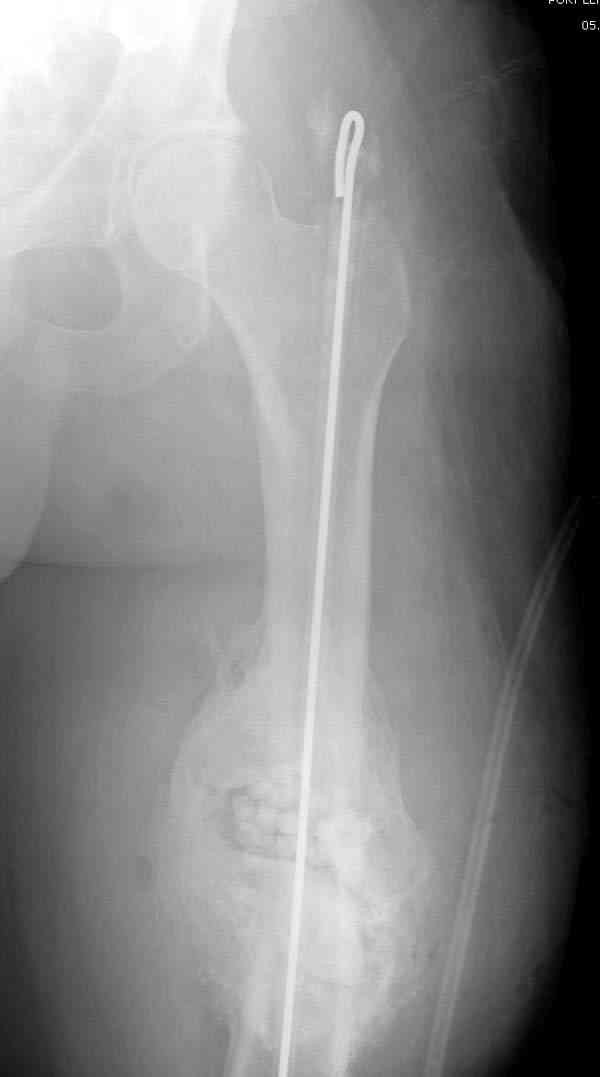

удаление

подготовка гвоздя

7-8 послеоперационные